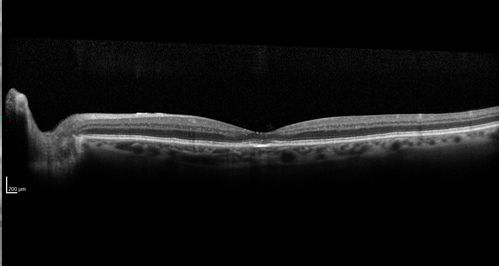

Confluent Soft Drusen with Subetinal Fluid - Right Eye

Asymptomatic 85 year old man.  OCT shows pocket of subfoveal fluid in the center of the macula.  This could be mechanical from the drusen preventing the retina from settling down.  Testing did not reveal a CNVM and subsequent OCT 6 weeks later showed no change in structure.